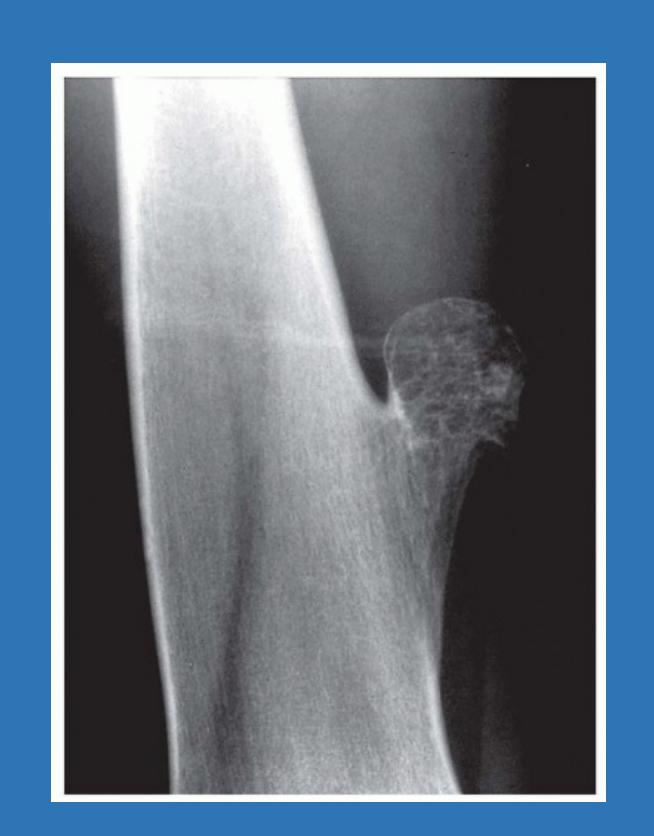

| Look | Compare both limbs, Skin, Muscle bulk, bony landmarks, hair distribution | Assess symmetry, signs of trauma, inflammation, muscle atrophy, structural changes | Visual examples - Skin, Muscle, Bone, Joint: ![]() ![]() ![]() ![]() ![]() ![]() | Swelling, scars, discoloration, hair changes, muscle wasting, bony protrusions, angulation, redness |

| Back of knee | Assess for posterior aspect abnormalities, such as Baker’s cyst | Posterior aspect: ![]() | Swelling, tenderness, masses in the popliteal fossa | |

| Feel | Tenderness (General, Localized): Quadriceps, Patella, Patellar tendon, Tibial tuberosity, Origin, and insertion of collateral ligaments, ACL, MCL | Identify areas of pain and inflammation in relevant structures | Tenderness - General: Tenderness - Localized: Medial Structures (Tibial Tuberosity, Joint Line, Medial Tibial Condyle, Patella, Medial Femoral Condyle, Joint Space, MCL): ![]() Lateral Structures (Quadriceps, Patella, Tibial Tuberosity, Head of Fibula, LCL, Lateral joint line): ![]() | Localized pain upon palpation |

| Joint-line tenderness, medial and lateral | Assess for meniscal or collateral ligament pathology | Joint lines: ![]() | Pain upon palpation along the joint line | |

| Anatomic Examination: Bone (Patella, Tibial Tuberosity, head of Fibula) | Assess bony landmarks for tenderness or deformity | Bone Landmarks: ![]() | Tenderness, mass, crepitus, abnormal landmarks | |

| Anatomic Examination: Joint assessment | Assess for swelling, effusion, crepitation, and synovial thickening | Joint Assessment: ![]() | Presence of swelling, effusion, crepitation, synovial thickening, joint line tenderness | |